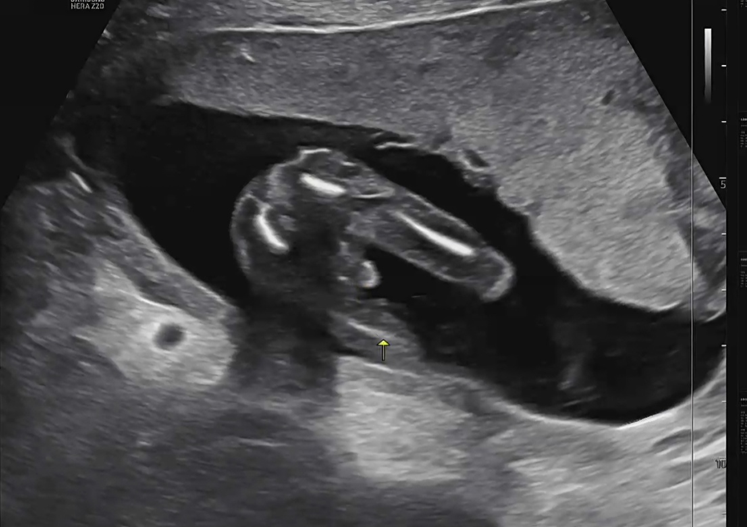

② 초음파 시간: 또리의 폭풍 성장과 성별 힌트! 📢

검사 후에는 또리의 상태를 확인하는 정기 초음파 시간이 이어졌어요.

- 📏 아기의 성장: 12주차 때 젤리곰 같던 또리가 이제는 제법 사람 형태를 갖추고 있었어요! 키는 벌써 12cm에 몸무게는 100g을 훌쩍 넘겼다고 하시네요. 선생님께서 "이제 양수 속에서 수영도 하고, 손으로 발을 만지작거리기도 해요!"라고 설명해 주시는데, 그 모습이 너무 신기해서 눈물이 핑 돌았답니다.

- 👣 힘찬 움직임: 안정기 접어들면서 엄마는 아직 미세하지만, 초음파로 보니 또리는 팔다리를 아주 힘차게 움직이며 놀고 있더라고요! 건강하게 잘 자라주는 모습에 감사했어요.

- 📢 대망의 성별 힌트! : 16주차는 보통 성별을 90% 이상 예측할 수 있는 시기이죠. 선생님께서 초음파 화면을 보여주시며 조심스럽게 '다리사이에 뭐가 보이죠??'라고 하시네요.. (딸을 원했던 아빠는 살며시 눈물을 감추는...ㅎㅎ) 제 2의 여자친구 만들어주기 싫었는데.. 쌤통이다 !!ㅋㅋㅋㅋㅋㅋㅋ